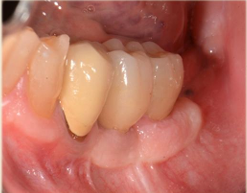

• Tecniche di aumento tessuti molli perimplantari

• Gestione tempi protesici